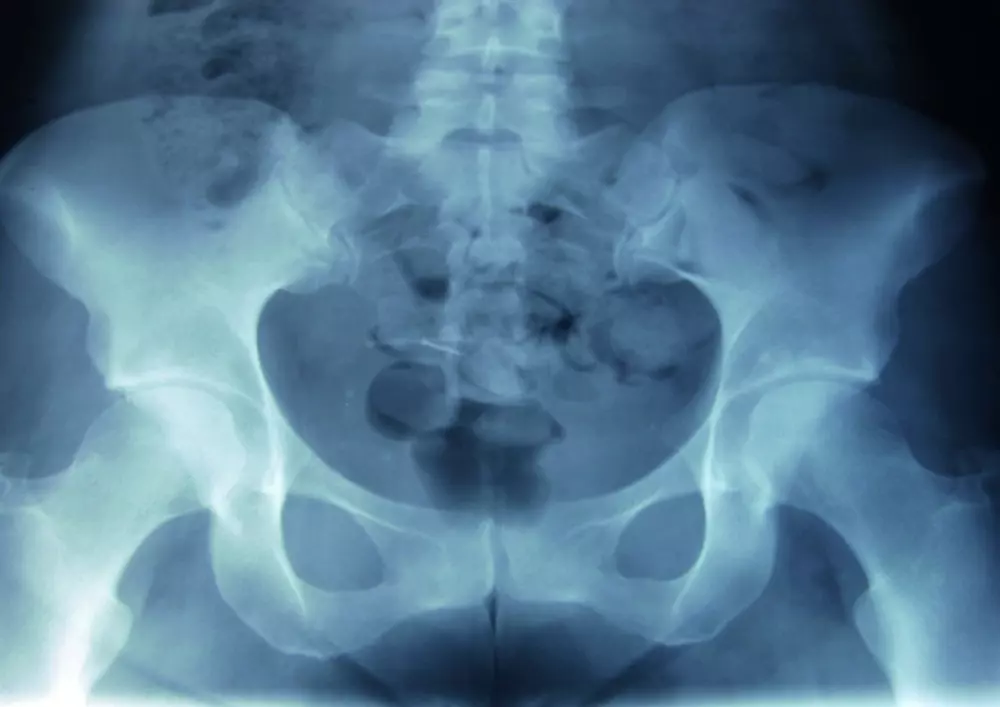

W dziale „Z praktyki gabinetu” znajdą Państwo tekst pt. „Metoda McKenziego w rwie kulszowej. Opis przypadku”. Bóle kręgosłupa dotyczą bardzo dużej części społeczeństwa, co może mieć źródło w siedzącym trybie życia i ograniczeniu aktywności ruchowej. Choć lekarze i fizjoterapeuci nieustannie poszukują nowych metod walki z bólem, do najpopularniejszych wciąż należy właśnie metoda McKenziego. Krzysztof Czupryniak przedstawia przypadek 32-letniej kobiety, spędzającej większość czasu w pozycji siedzącej, jednak uprawiającej przy tym jogging 3 razy w tygodniu. Opisuje badanie przedmiotowe oraz poszczególne sesje fizjoterapii z wykorzystaniem wspomnianej metody.